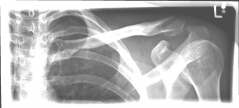

Images: A lateral clavicle fracture was treated with a hook plate. The hook is fixed under the acromioclavicular, while screws anchor the plate in the collarbone.